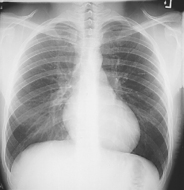

Correct CR location to the midchest (T7) allows for accurate collimation and protection of the upper radiosensitive region of the neck area. It also prevents exposure to the dense abdominal area below the diaphragm, which produces scatter and secondary radiation to the radiosensitive reproductive organs.

T7 for the PA chest can be located posteriorly in reference to C7, the vertebra prominens. Level of T7 is 7-8 inches (18-20 cm) below the vertebra prominens.

• Center CR to T7 region. Top of IR will be approximately 2″ (5 cm) above shoulders on average patient.

• Center thorax bilaterally to IR borders with equal margins on both sides; ensure there is no rotation of thorax.